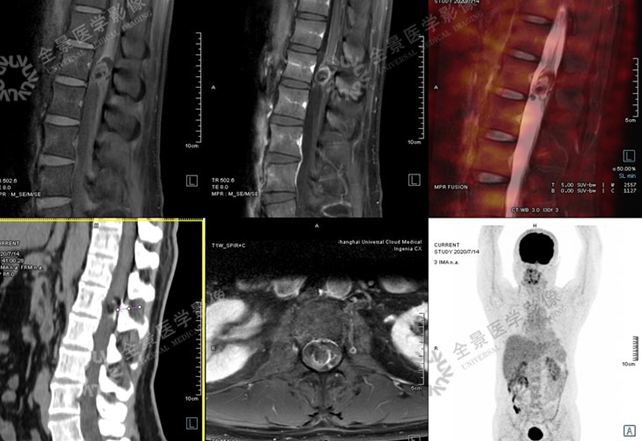

骨关节

案例 :骨巨细胞瘤

T2WI不均匀等信号,

PET/CT显示:T3骨质破坏并周围软组织肿块形成,FDG明显摄取增高。

增强扫描明显强化